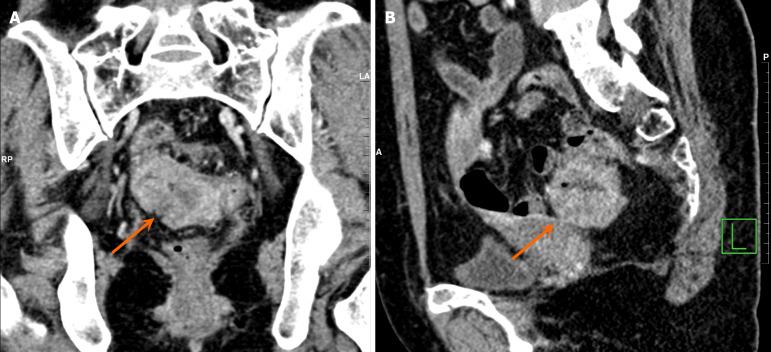

Breast cancer and rectal cancer associated with Lynch syndrome: A case report.

This paper presents a comprehensive review of clinical diagnosis and treatment data from a patient with LS-associated BC and rectal cancer. Moreover, screening data and management guidelines, as well as relevant literature on LS, are included in this report. This study summarizes the molecular pathogenesis, clinicopathological features, and screening and management protocols for LS-associated BC and rectal cancer.